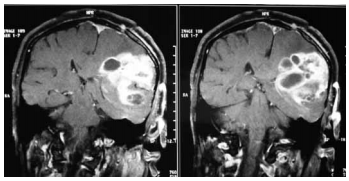

Uma mulher com cinquenta e três anos de idade foi admitida em um hospital apresentando, havia dois meses, quadro de cefaleia, hemiparesia à direita, náuseas e dificuldade na fala — todos de caráter progressivo. A paciente negou febre e não houve crise convulsiva nem alterações comportamentais. Os resultados do exame de ressonância magnética contrastada do crânio são mostrados na figura precedente. Com relação a esse caso clínico, julgue o item seguinte considerando o resultado das imagens. Deve-se iniciar o tratamento dessa paciente com anticonvulsivante profilático para se prevenir uma primeira convulsão.

Uma mulher com cinquenta e três anos de idade foi admitida em um hospital apresentando, havia dois meses, quadro de cefaleia, hemiparesia à direita, náuseas e dificuldade na fala — todos de caráter progressivo. A paciente negou febre e não houve crise convulsiva nem alterações comportamentais. Os resultados do exame de ressonância magnética contrastada do crânio são mostrados na figura precedente. Com relação a esse caso clínico, julgue o item seguinte considerando o resultado das imagens. No caso em questão, caso ocorram síncopes causadas por tosse, espirros ou por vômitos, elas refletirão reduções temporárias da pressão de perfusão cerebral, associadas a ondas platô — tipo A de Lundberg — na pressão intracraniana.

Uma mulher com cinquenta e três anos de idade foi admitida em um hospital apresentando, havia dois meses, quadro de cefaleia, hemiparesia à direita, náuseas e dificuldade na fala — todos de caráter progressivo. A paciente negou febre e não houve crise convulsiva nem alterações comportamentais. Os resultados do exame de ressonância magnética contrastada do crânio são mostrados na figura precedente. Com relação a esse caso clínico, julgue o item seguinte considerando o resultado das imagens. Os sintomas descritos no caso clínico podem ser reduzidos com a administração de dexametasona venosa em alta dose.

Uma mulher com cinquenta e três anos de idade foi admitida em um hospital apresentando, havia dois meses, quadro de cefaleia, hemiparesia à direita, náuseas e dificuldade na fala — todos de caráter progressivo. A paciente negou febre e não houve crise convulsiva nem alterações comportamentais. Os resultados do exame de ressonância magnética contrastada do crânio são mostrados na figura precedente. Com relação a esse caso clínico, julgue o item seguinte considerando o resultado das imagens. A espectroscopia por ressonância magnética nessa paciente evidenciará, no local da lesão, aumento de N-acetilaspartato e redução de colina.